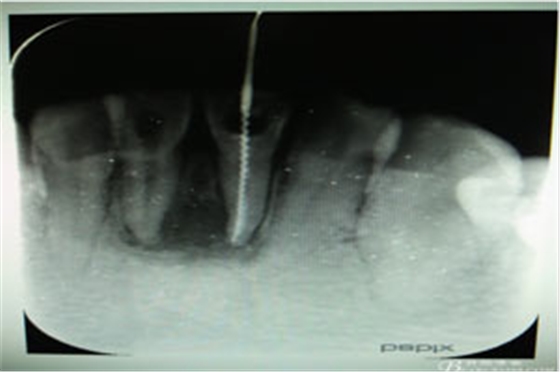

圖4.31插入診斷絲照片